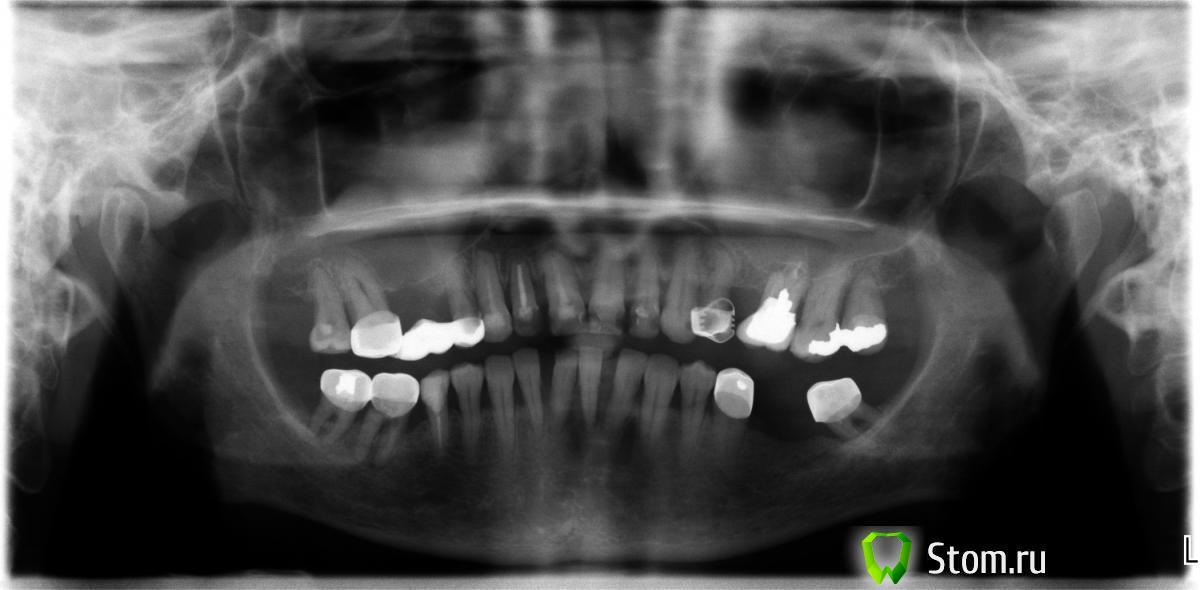

Нат Опубликовано 12 января, 2012 Поделиться Опубликовано 12 января, 2012 6-ка верхняя, слева, со штифтом под коронкой. Врач посоветовал удалить маме моей. Но с другой стороны. у папы была похожая ситуация и ему зуб "вытянули", пока второй год стоит, только вот он не помнит, что с ним делали. Посоветуйте, пожалуйста. Ссылка на комментарий

Нат Опубликовано 12 января, 2012 Автор Поделиться Опубликовано 12 января, 2012 К сожалению, на руках только такой. Ссылка на комментарий